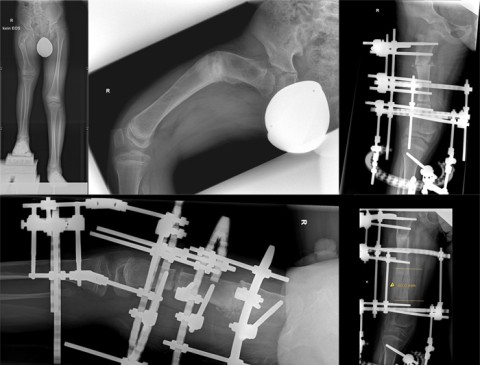

Die finanzielle und auch die Wohnsituation der Familie ist schlecht. Die medizinische Infrastruktur in der Gegend ist für ihn auch nicht gegeben. Folglich waren und sind die Möglichkeiten, ein verkürztes Bein zu behandeln, in seiner Heimat nicht vorhanden. Zwar fand 2017 eine erste Operation zur Streckung des Beines in Usbekistan statt. Diese brachte aber nicht gewünschten Erfolg. Vielmehr kam es anschliessend zu einer sehr starken zusätzlichen, fast 80-°-igen Deformierung des Oberschenkelknochens neben der sowieso bereits vorbestehenden Längendifferenz von 15 cm. Und schliesslich waren auch die finanziellen Mittel der Eltern am Ende, um eine weitere Behandlung zu ermöglichen.

Im September ging die Reise dann weiter in die Schweiz zur Schulthess Klinik. In einer 4-stündigen Operation befestigten unsere Spezialisten der Kinder- und Jugendorthopädie von aussen einen Ilizarov-Ringfixateur am Oberschenkelknochen. «Wir konnten dank hervorragender Teamarbeit schon während der Operation die schwere Fehlstellung korrigieren. Es war nicht ganz einfach, einen so kurzen Knochen an zwei Stellen zu trennen, die Fehlstellung zu korrigieren und das Ganze in den Ringfixateur zu integrieren», erklärt Dr. med. univ. Hannes Manner die Herausforderungen der Operation. «Zeitgleich bereiteten wir die anschliessende Verlängerung des Oberschenkelknochens vor.»

Zurück im Friedensdorf sorgte das dortige medizinische Fachpersonal für die weitere Betreuung. Dazu gehörte auch, regelmässig mittels Justierung des Fixateurs die Beinverlängerung Millimeter um Millimeter voranzutreiben und die Eintrittsstellen zu reinigen und zu pflegen. So konnte in den anschliessenden drei Monaten der Knochen um ganze 8 cm verlängert werden. Eine begleitende Physiotherapie sorgte zudem für die richtige Bewegung und den Aufbau der Muskeln. Dort veranlasste Röntgenbilder hielten unsere Kinderorthopädie über die Beinverlängerung und den Heilungsverlauf auf dem Laufenden.

Im März ging die Reise abermals zu uns in die Schweiz. In einer ambulanten Operation entfernten wir den Fixateur und stabilisierten das Bein in einem Gips.